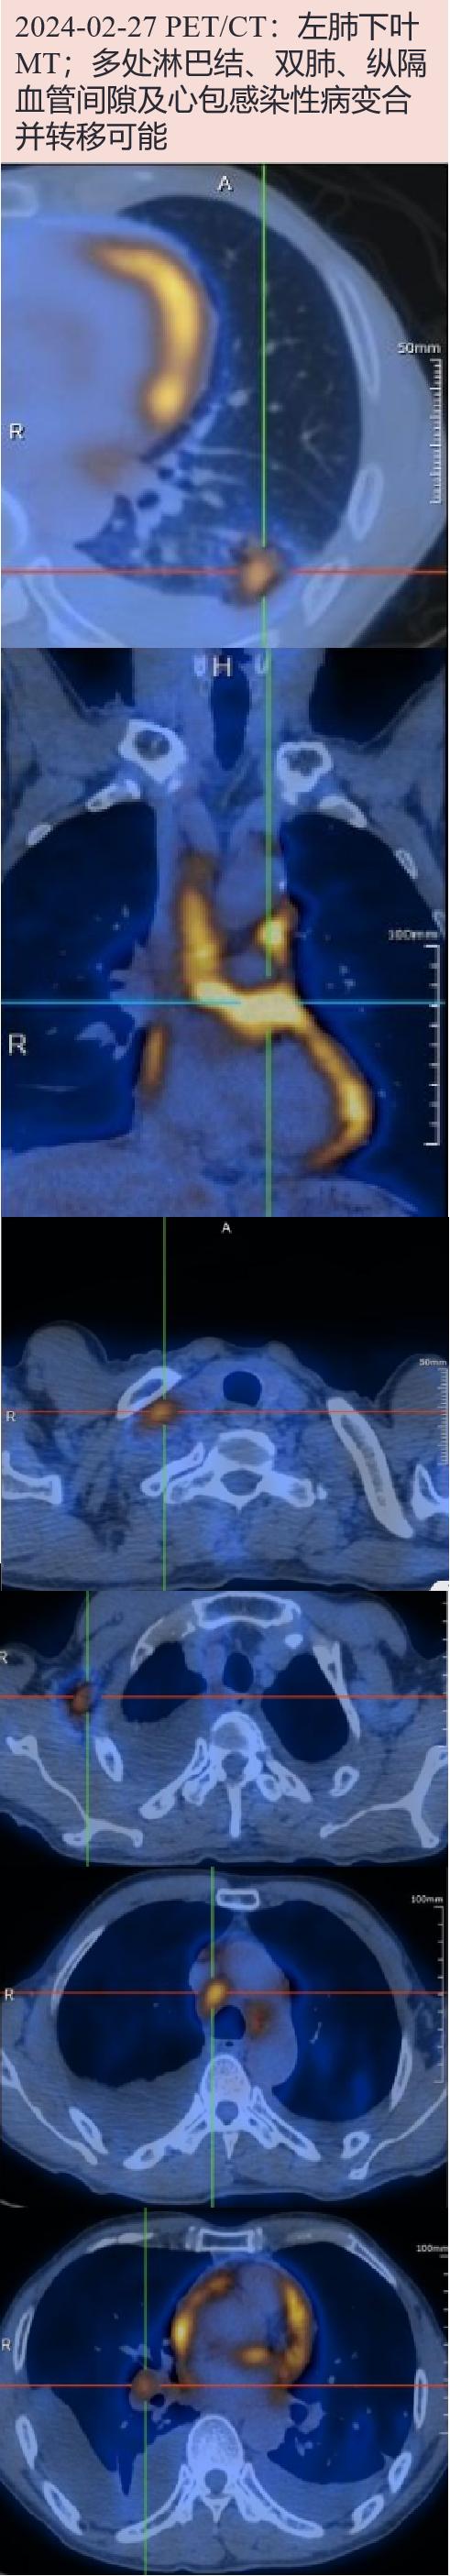

2024-02-27 PET/CT:左肺下叶MT(分叶状实性结节,大小约20.0×17.0mm,SUVmax 7.8);多处(双肺门、纵隔、右侧腋窝、双侧锁骨区及颈部、膈上心周、右侧肋间、腹腔及腹膜后,心包增厚伴糖代谢异常增高,SUVmax10.9;右锁骨区肿大淋巴结大小25.3×14.3mm,SUVmax 5.9)淋巴结、双肺、纵隔血管间隙及心包感染性病变合并转移可能。

2024-02-28 患者体温平, 胸水引流每日少于200ml,予拔管出院,继续异烟肼0.3g qd+利福平0.45g qd+乙胺丁醇0.75g qd+吡嗪酰胺1g qd抗结核;PET/CT提示、腋窝、肺门、纵隔淋巴结代谢增高均位于右侧,考虑结核病累及多处淋巴结可能大,肺鳞癌淋巴结转移可能小,临床分期考虑T1N0M0可能,嘱至呼吸内科、胸外科评估肺癌治疗。出院后随访

患者老年男性,活动后气促伴咳嗽3月,胸CT:两肺多发结节,双侧锁骨上、右腋下、肺门、纵隔多发肿大淋巴结,两侧胸腔积液、心包增厚伴积液。PET/CT:左肺下叶结节病灶代谢增高考虑MT;多处(双肺门、纵隔、右侧腋窝、双侧锁骨区及颈部、膈上心周、右侧肋间、腹腔及腹膜后)淋巴结、双肺、纵隔血管间隙及心包感染性病变合并转移可能。左下肺结节穿刺病理为低分化鳞癌。右侧锁骨上淋巴结穿刺病理为肉芽肿性病变,抗酸染色可疑阳性,组织XPERT.TB 阳性、mNGS检出结核分枝杆菌复合群。故考虑结核病累及肺、淋巴结明确,胸膜及心包累及可能;合并左下肺低分化鳞癌可能大,淋巴结转移不除外。

在临床工作中,我们也要警惕陷入“一元论”的思维,因病理确诊而单一诊断为某一疾病,认为肺部多发结节及远处淋巴结肿大为转移灶,忽略了合并有其他疾病的可能。仔细阅CT片,该患者肺部其他病灶更倾向肺结核表现,T-SPOT阳性,且患者PET/CT检查见肺门、纵隔、腋窝、锁骨上淋巴结明显高代谢的均位于右侧,不符合左下肺癌常见转移部位,因此针对右侧锁骨上淋巴结进行了穿刺活检,病理提示肉芽肿性变,抗酸染色可疑阳性,XPERT.TB弱阳性,考虑淋巴结结核诊断明确,也间接支持其他淋巴结为结核可能。